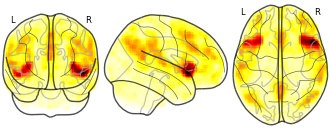

seed connectivity maps - Controls Ayahuasca: dorsal insula seed

Mean group seed connectivity maps derived from rs-fMRI data from healthy individual before and 24h after ayahuasca or placebo intake.

homo sapiens

fMRI-BOLD

group

rest eyes closed